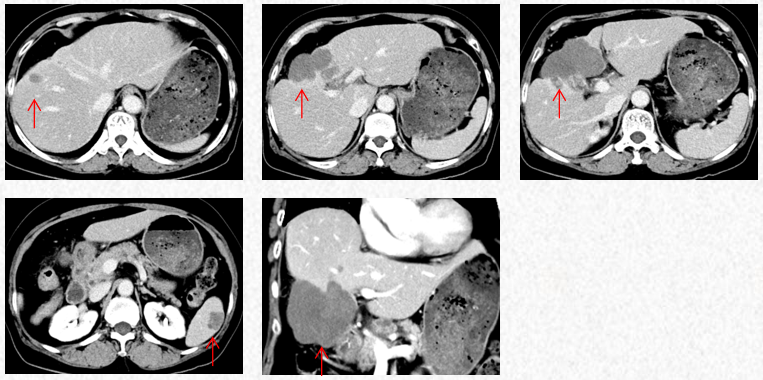

2023-3-19复查胸腹CT图片,最佳疗效评估为PR。

2023-3-19胸腹CT:肝肿物最大横截面积91*60mm,脾脏转移瘤(19*12mm)

2023-5-22胸腹CT:肝肿物最大横截面积86*58mm,脾脏转移瘤(19*12mm)

2023-7-15胸腹CT:肝肿物最大横截面积86*58mm,脾脏转移瘤(19*12mm)